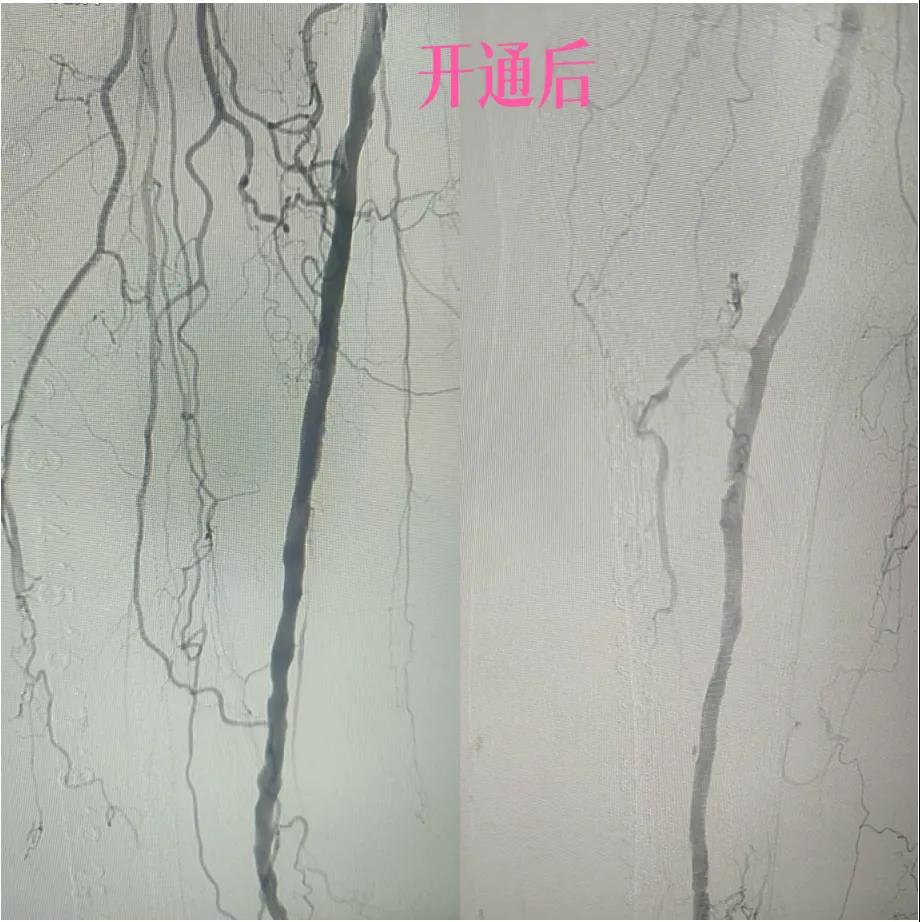

漯河市中醫(yī)院:微創(chuàng)介入:球囊擴(kuò)張術(shù),“撐”開生命通道

近日,漯河市中醫(yī)院外二科血管外科介入團(tuán)隊(duì)利用微創(chuàng)介入技術(shù)成功保住一患者患肢。

據(jù)悉,患者以“右足足趾疼痛伴第三足趾壞疽4月余”為主訴來院就診,查體患者右足第三趾末端呈壞疽狀,已結(jié)痂,足趾根部及足背部紅胖、壓痛,右側(cè)足背動(dòng)脈,脛后動(dòng)脈搏動(dòng)未觸及,下肢深靜脈血管彩超:雙側(cè)下肢深動(dòng)脈粥樣斑塊形成,右側(cè)腘動(dòng)脈流速減低,右側(cè)脛后動(dòng)脈及足背動(dòng)脈不顯示(閉塞?)

為了挽救患者的患肢,避免截肢,外二科血管外科介入團(tuán)隊(duì)經(jīng)過縝密的術(shù)前討論和評(píng)估,決定采用目前微創(chuàng)介入技術(shù)——下肢動(dòng)脈藥涂球囊擴(kuò)張成形術(shù)(DCB)。

2.  “探路”與“疏通”:在先進(jìn)的DSA(數(shù)字減影血管造影)設(shè)備實(shí)時(shí)引導(dǎo)下,猶如擁有了“透視眼”,導(dǎo)管導(dǎo)絲巧妙穿越病變血管的狹窄、閉塞段。這需要極高的技巧和對(duì)血管解剖的深刻理解。

3.  “球囊發(fā)力”:到達(dá)目標(biāo)閉塞段后,將未充氣的球囊導(dǎo)管送至病變部位。隨后,精準(zhǔn)控制壓力,使球囊緩慢充盈擴(kuò)張,如同在血管內(nèi)部進(jìn)行精細(xì)的“拓荒”,將堵塞的斑塊擠壓、塑形,撐開狹窄的血管腔。

4.  即刻“見證”:再次造影顯示,原本狹窄閉塞的血管段血流恢復(fù)通暢!足部遠(yuǎn)端血管顯影較前明顯改善。手術(shù)過程順利,患者靜息痛較前明顯改善。